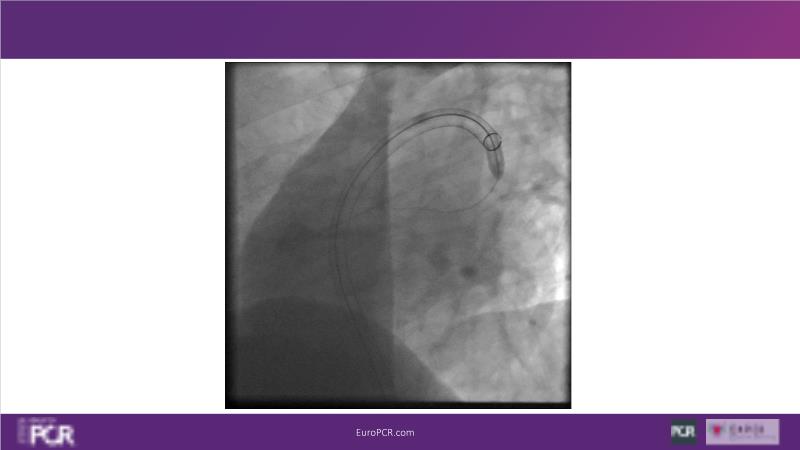

Why mechanical thrombectomy should be considered in the management of acute pulmonary embolism

In this EuroPCR 2024 session, study the case of a patient with high-risk pulmonary embolism and another with intermediate to high-risk pulmonary embolism, delve into discussions on clinical evidence for mechanical thrombectomy in pulmonary embolism, acquire skills to evaluate eligibility for mechanical thrombectomy, and learn how to integrate such technique in local pulmonary embolism patient pathway.